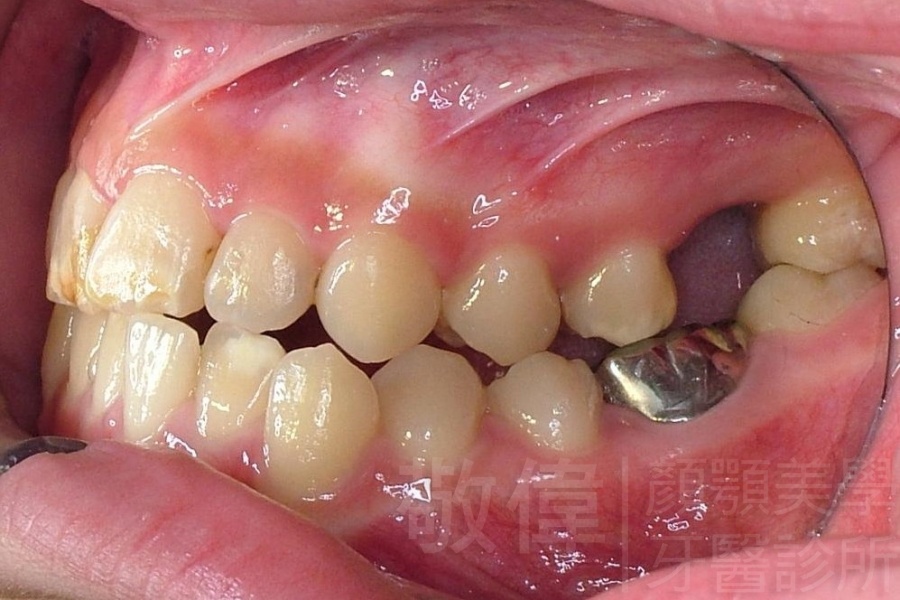

齒顏矯正/戽斗、亂牙、爛牙,變身 免植牙的健牙美女

變臉矯正,原來戽斗妹跟大歪臉變成自信正妹

經由本院3D數影X光影像儀分析、與3D齒顎顏矯正技術,再配合口腔顎面正顎專科醫師施以正顎手術治療,雙方共同合作,使患者臉部外觀有很好的改善,大歪變小歪,產生了天南地北的大改變,她的人生也整個變得不一樣。

因為矯正與正顎手術的配合,使「戽斗妹」變成了「陽光正妹」,完全的改變了她的人生,在面對各種場合、與人交際都散發出自信微笑。所以,奉勸家長,如果小朋友有臉顎畸型的問題,應該考慮配合做這種簡單、安全、有效的正顎手術。